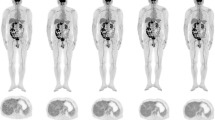

All patients fasted for 6 h before 18F-FDG administration. The list-mode PET data were acquired using a total-body PET/CT scanner with 194-cm-long axial FOV (uEXPLORER, United Imaging Healthcare, Shanghai, China) 60 min after 18F-FDG injection (3.7 ± 0.37 MBq/kg [0.1 ± 0.01 mCi/kg] activity per body weight). Low-dose CT scans of the whole body were obtained by uEXPLORER (tube current 10 mA, voltage 100 kV, rotation time 0.5 s, pitch 1.0125, collimation 80 × 0.5 mm) were reconstructed in a 512 × 512 matrix for attenuation correction. The acquisition time of emission images was 600 s, and PET images were reconstructed into 600, 300, 60, 40, and 20 s (Fig. 1). All PET images were reconstructed using ordered subset expectation maximization (OSEM) and setting a spectrum of parameters, for instance, time-of-flight and PSF modeling, 3 iterations, 20 subsets, matrix 256 × 256, slice thickness of 2.89 mm, pixel size 2.34 × 2.34 × 2.89 mm3 with a Gaussian post-filter (3 mm), and all necessary correction methods including attenuation and scatter correction. All image evaluation has been performed in a commercial medical image processing workstation (uWS-MI, United Imaging Healthcare).

18F-FDG PET image of a 1.9-year-old male patient weighted 10 kg with Langerhans cell histiocytosis was reconstructed into 600, 300, 60, 40, and 20 s shown in MIP and axial view (a–e), representing full dose, 1/2 dose, 1/10-dose, 1/15-dose, and 1/30-dose, respectively. The overall image scores of 5, 4, 3, and 2 were given to the group 300, 60, 40, and 20 s according to axial view images. Data in the paranthses were estimated effective dose

Micro-lesion detectability

A total of 33 18F-FDG-avid suspected micro-lesions with a mean diameter of 8 ± 2 mm were identified on the PET images of G600s. Among these lesions, there were 19 in the lymph node, 3 in the bone, 3 in the subcutaneous tissue, 2 in the liver, and 6 in the other organs, and details are provided in Supplementary Table 3. Example serial PET images of 2 micro-lesions are presented in Fig. 3. In G300 s, G60s, and G40s, all suspected micro-lesions were identified by all 3 radiologists, with a lesion detection rate of 100% relative to G600s. In G20s, 32 (97%) ROIs were identified by the 3 radiologists, where 1 lesion was missed (Fig. 3A) by all 3 radiologists.

MIP of the full dose image and axial view of the serial dose reduction image generated by reduced count. a An FDG-avid micro-lesion in the liver of a 7-year-old patient with neuroblastoma, with an SUVmax of 4.35 on the full-dose image. The lesion was identifiable as reduced down to 1/20-dose; were un-diagnosable at 1/30-dose. b A micro-lesion in the subcapsular region of the liver in a 3-year-old patient with Burkitt Lymphoma was diagnosable in all dose reduction setting